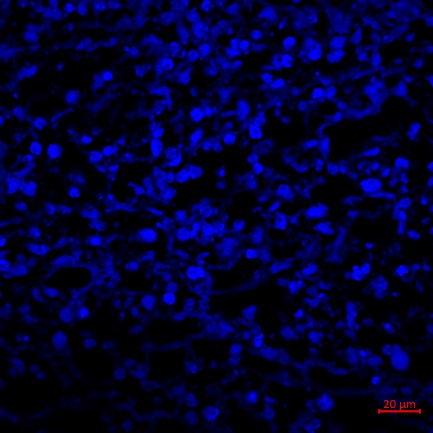

13、免疫荧光实验结果(小鼠肿瘤CBS抗体举例)

免疫荧光实验结果解读:选择激光共聚焦显微镜观察细胞核经DAPI染色后呈现蓝色,目的蛋白被AF594荧光染料标记而呈现红色。